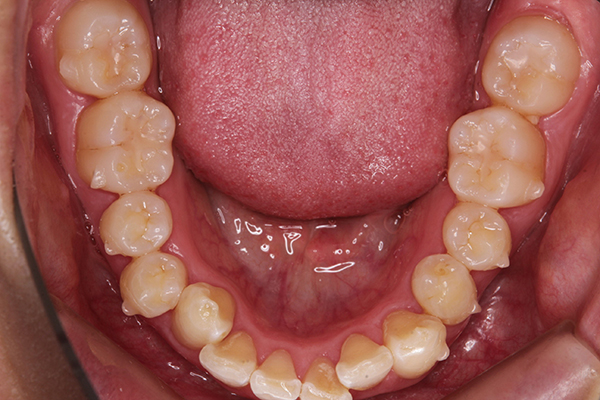

アタッチメントがついた写真が、こちら。

ぽつぽつと小さなものが並んでついていて

ちょっとかわいいです。笑